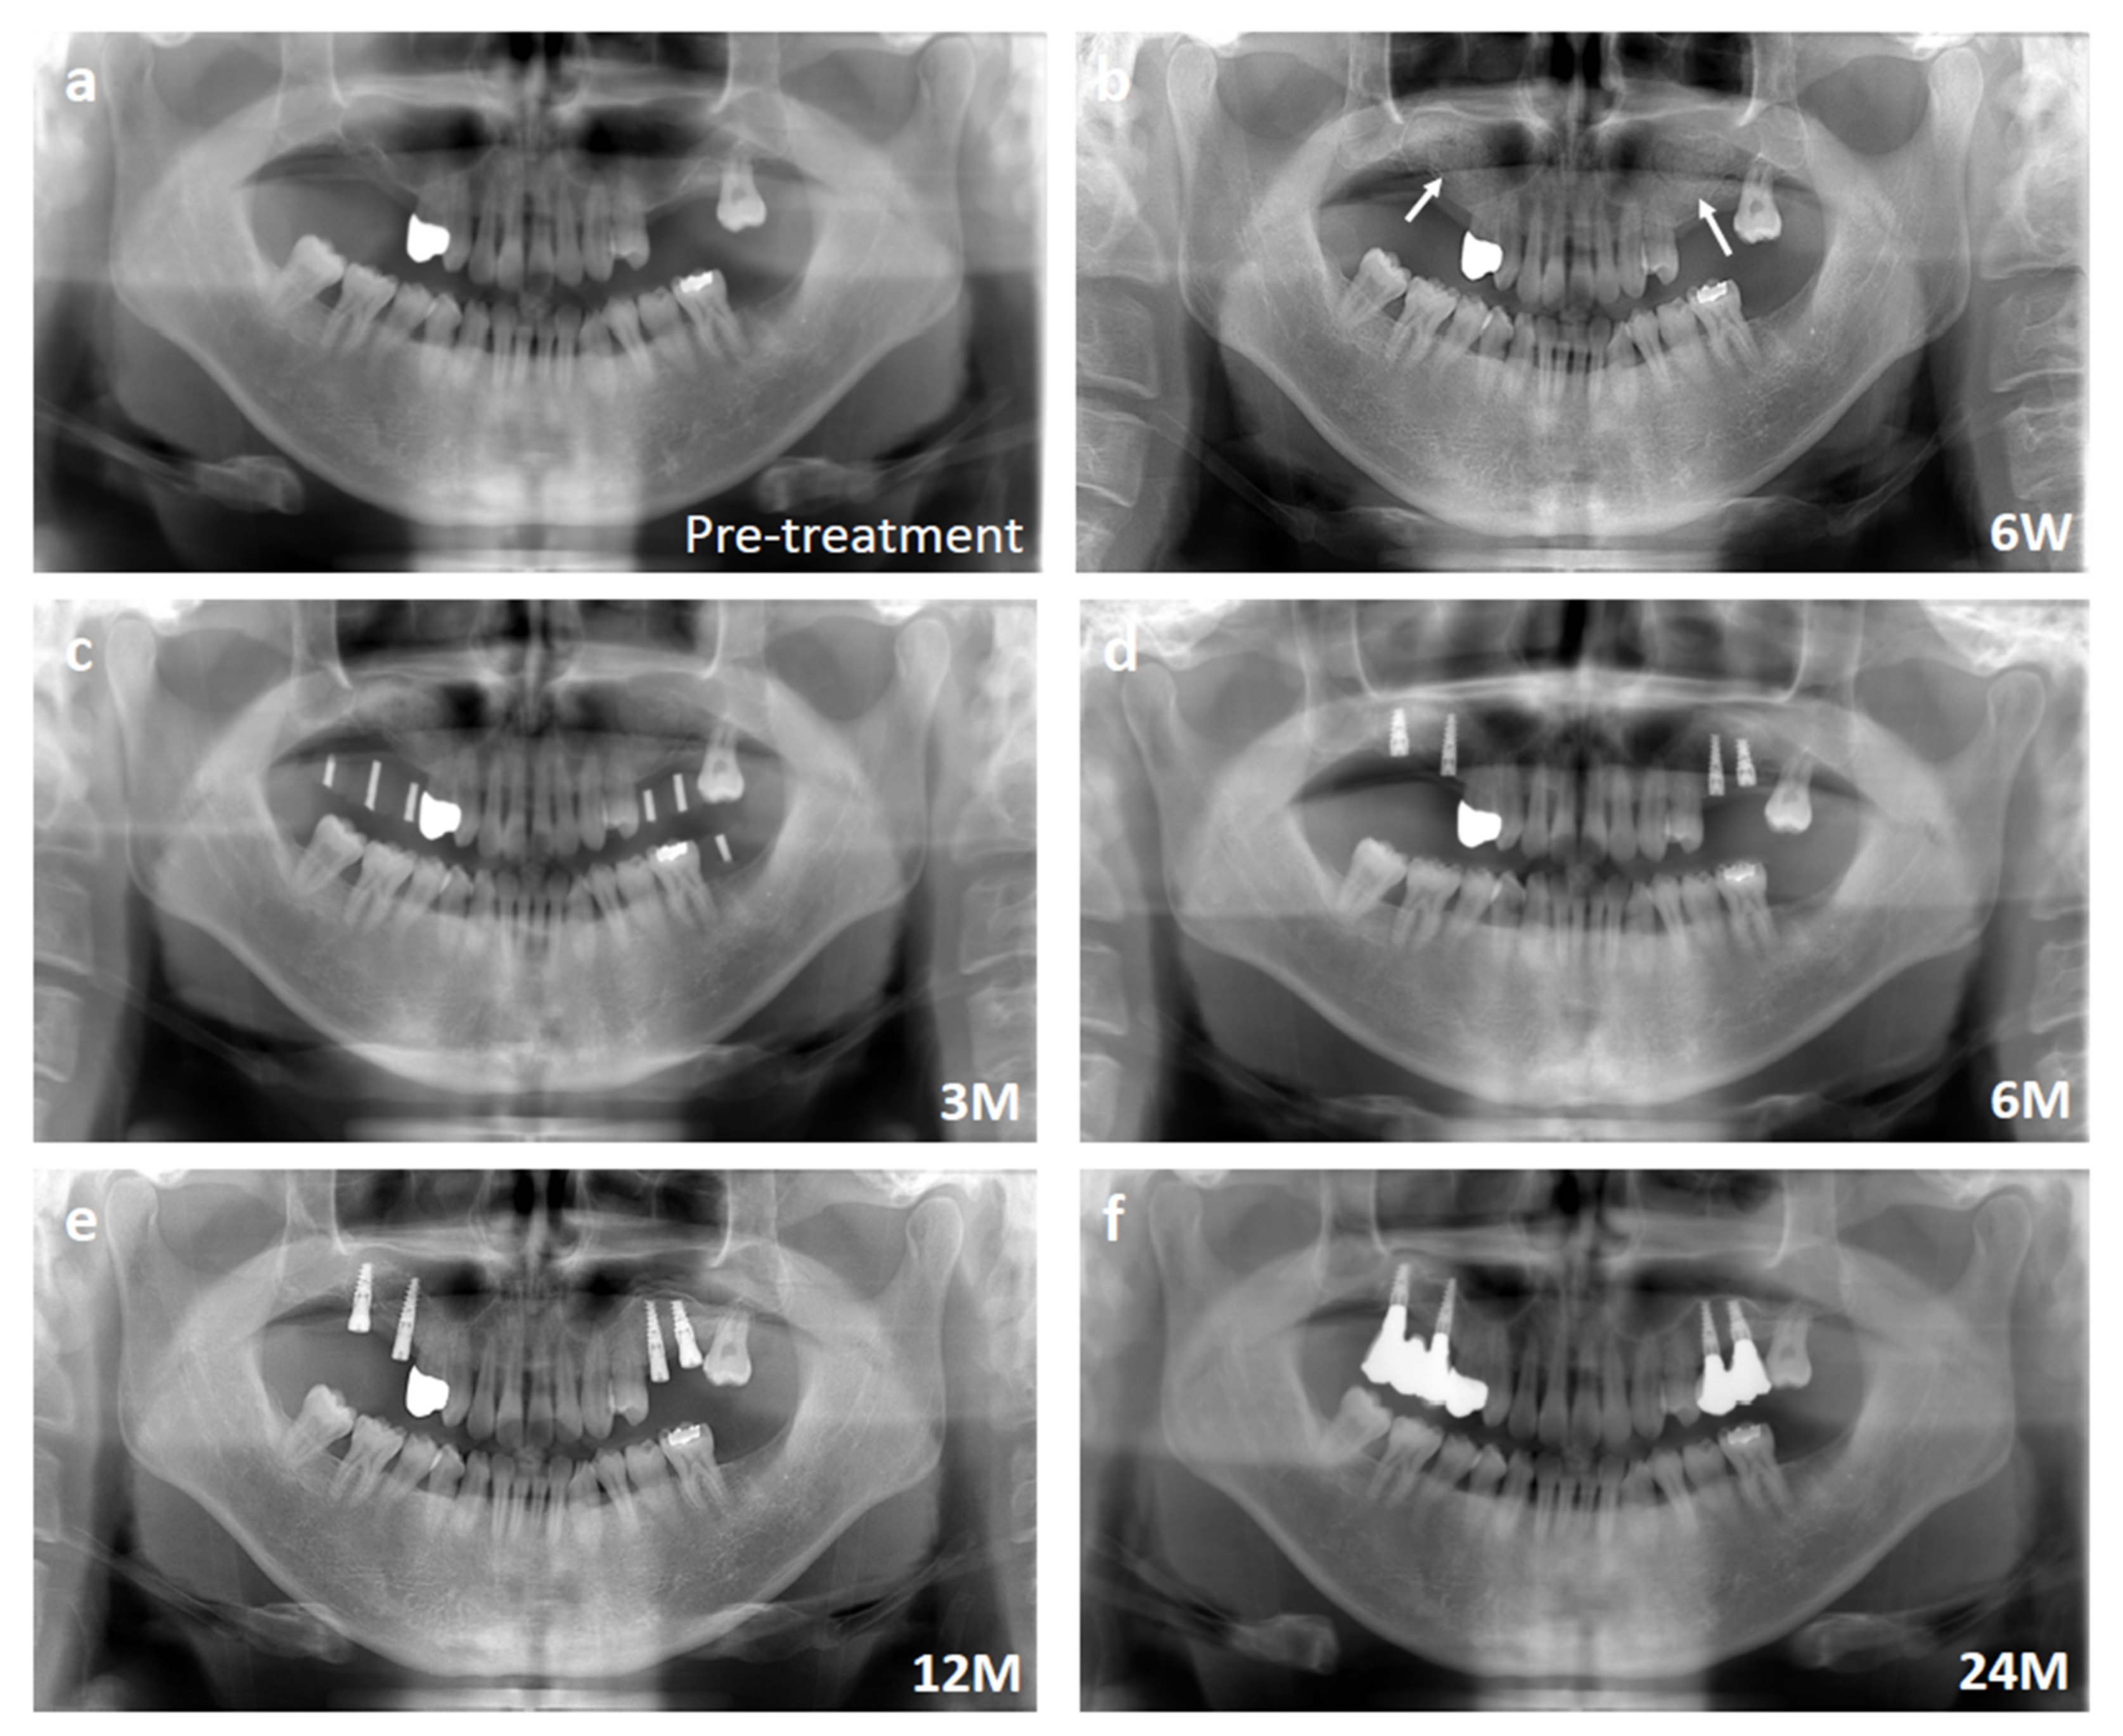

The time course of the bone regeneration was observed by panoramic radiography. Representative panoramic radiographs are shown in Figure 4, which is the same case shown in Figure 3. The sinus floor augmentation cases lacked sufficient alveolar bone height in the upper molar regions, and the height was <5 mm (Figure 4a). The tissue-engineered bone was transplanted into the sinus floor (Figure 4b). After three months, the transplantation sites were evaluated by panoramic radiography before implant installation (Figure 4c). After 6 months, the augmented sinus floor became flat, and the shape of the transplanted β-TCP granules was almost invisible at this stage (Figure 4d). At 6–12 months, the morphology of the regenerated bone became close to that of the surrounding existing bone and matured with clear separation of cortical and cancellous bone (Figure 4e), which was well-maintained for up to 24 months (Figure 4f).

Figure 4. Representative panoramic radiographs of the sinus floor augmentation case. (a) Pre-treatment. Note that the height of alveolar bone was extremely thin. (b) Six weeks after transplantation. White arrows indicate the elevated sinuses. (c) Three months after transplantation. (d) Six months after transplantation. (e) Twelve months after transplantation. (f) Twenty-four months after transplantation.